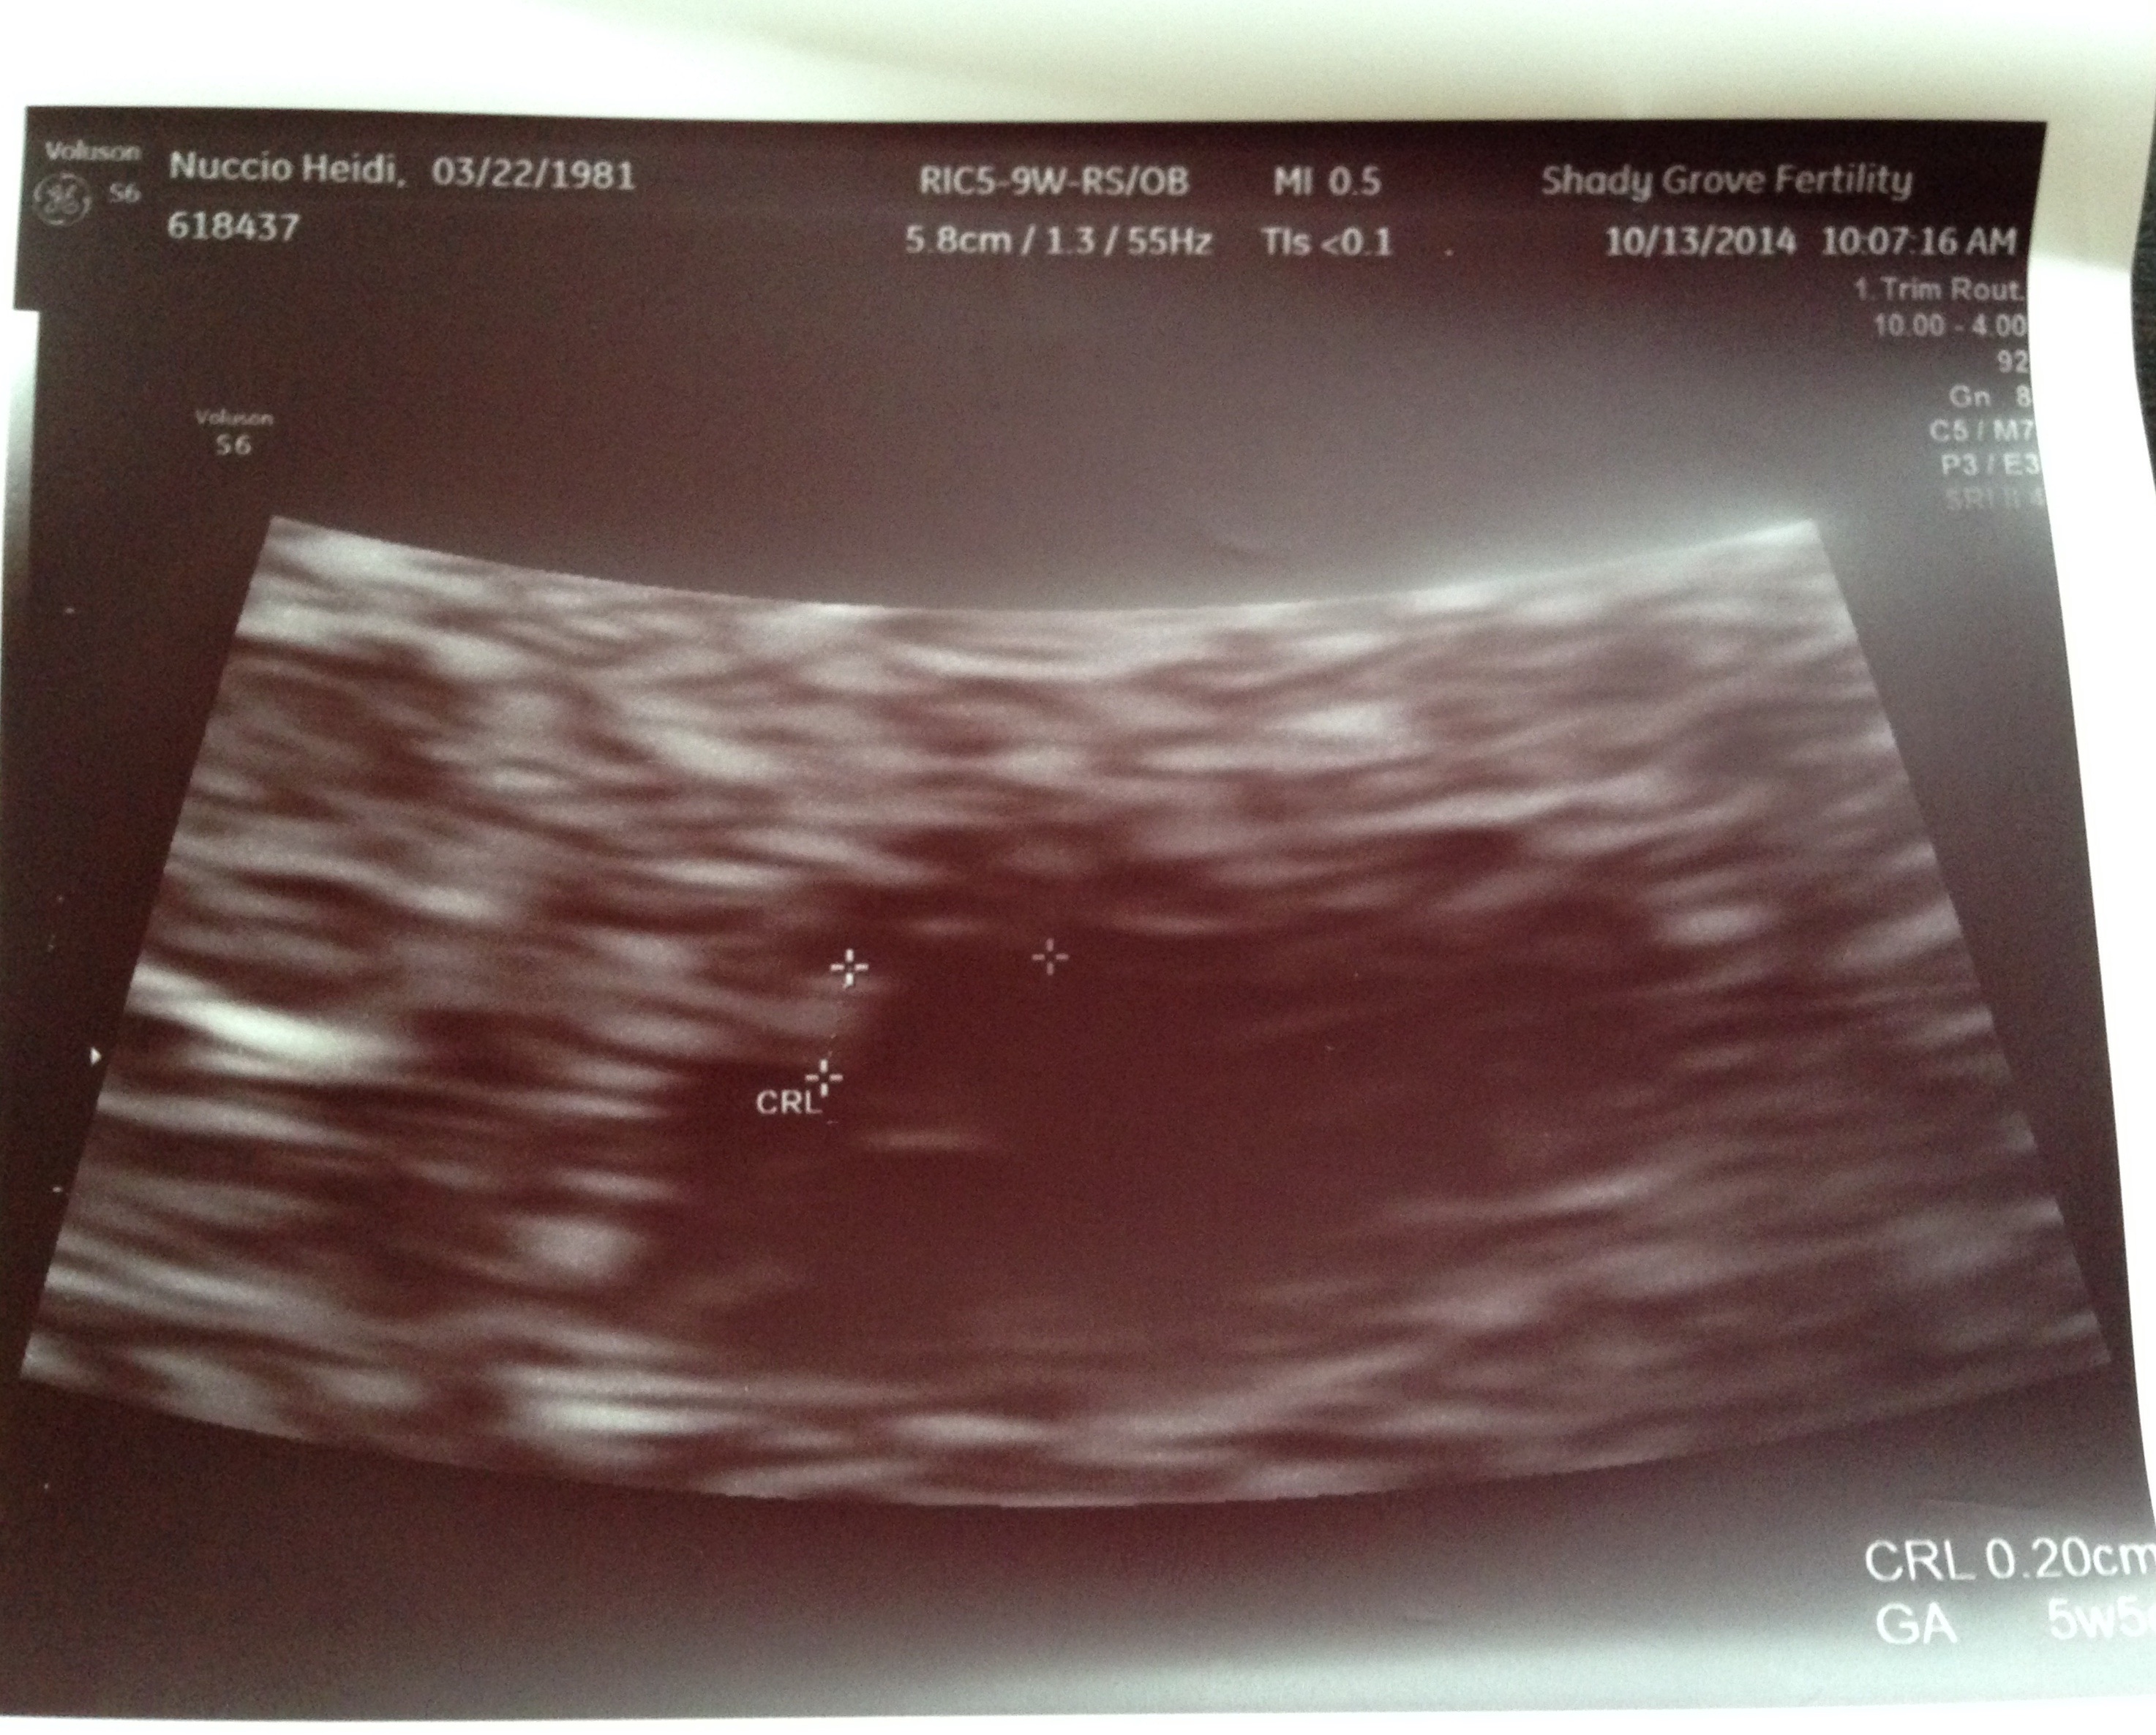

Had my first last night @ 6+1, too small to see anything, but definitely in the uterus and no cause for my spotting seen. OB said I looked more like 5 weeks. Spotting has since stopped (yay!) will repeat it November 3. Beta went from 4100 on Tues to 7100 yesterday, so I feel a bit of reassurance but will certainly feel better when I can see a heartbeat and fetus